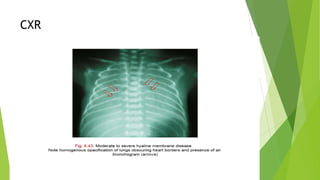

This document discusses respiratory distress and respiratory distress syndrome in neonates. It defines respiratory distress and describes the clinical signs. Various pulmonary and non-pulmonary causes are outlined. Respiratory distress syndrome, also known as hyaline membrane disease, is described in detail, including risk factors, pathophysiology, clinical presentation, investigations, complications, prevention, and treatment approaches like surfactant administration and nasal continuous positive airway pressure. The prognosis depends on gestational age and quality of care provided.